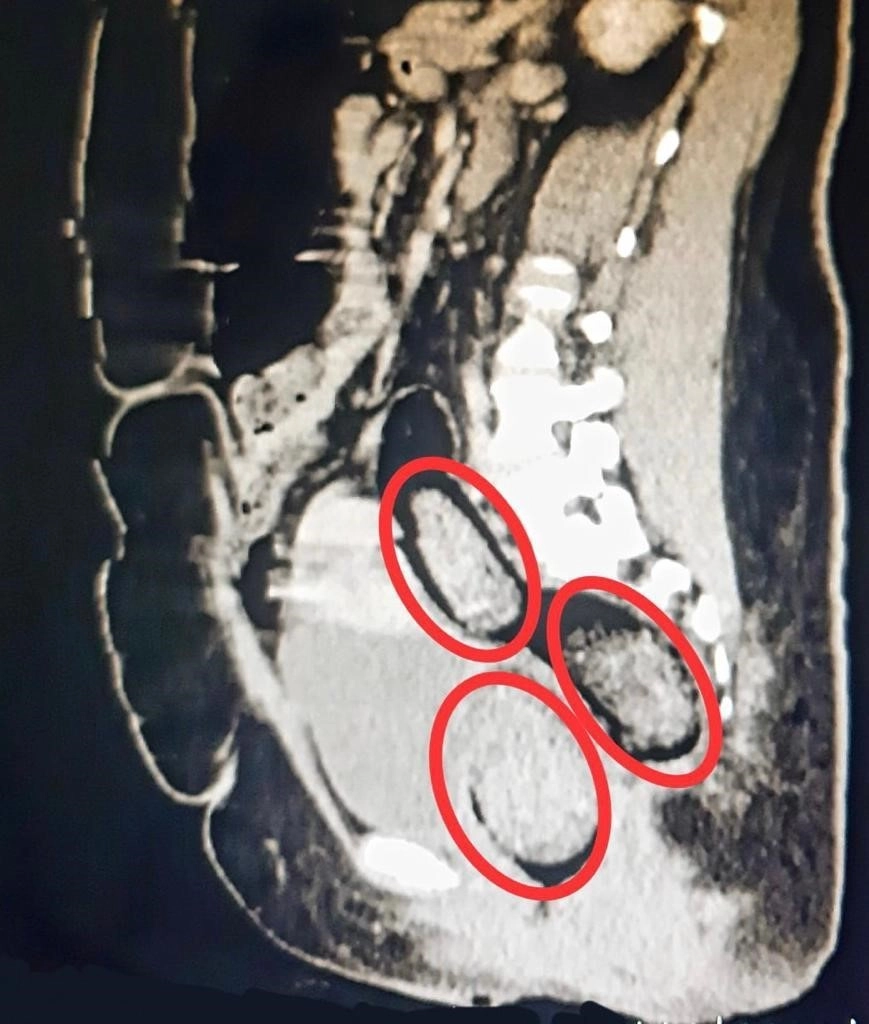

Otobüste gözaltına alınan Hadıs Aeınezad'in yapılan iç beden muayenesinde bağırsaklarında cisim olduğu tespit edildi. Hadıs Aeınezad'ın makadına saklanmış bir şekilde 3 parça 318 gram metamfetamin uyuşturucu maddesi cerrahi müdahaleyle çıkarıldı.